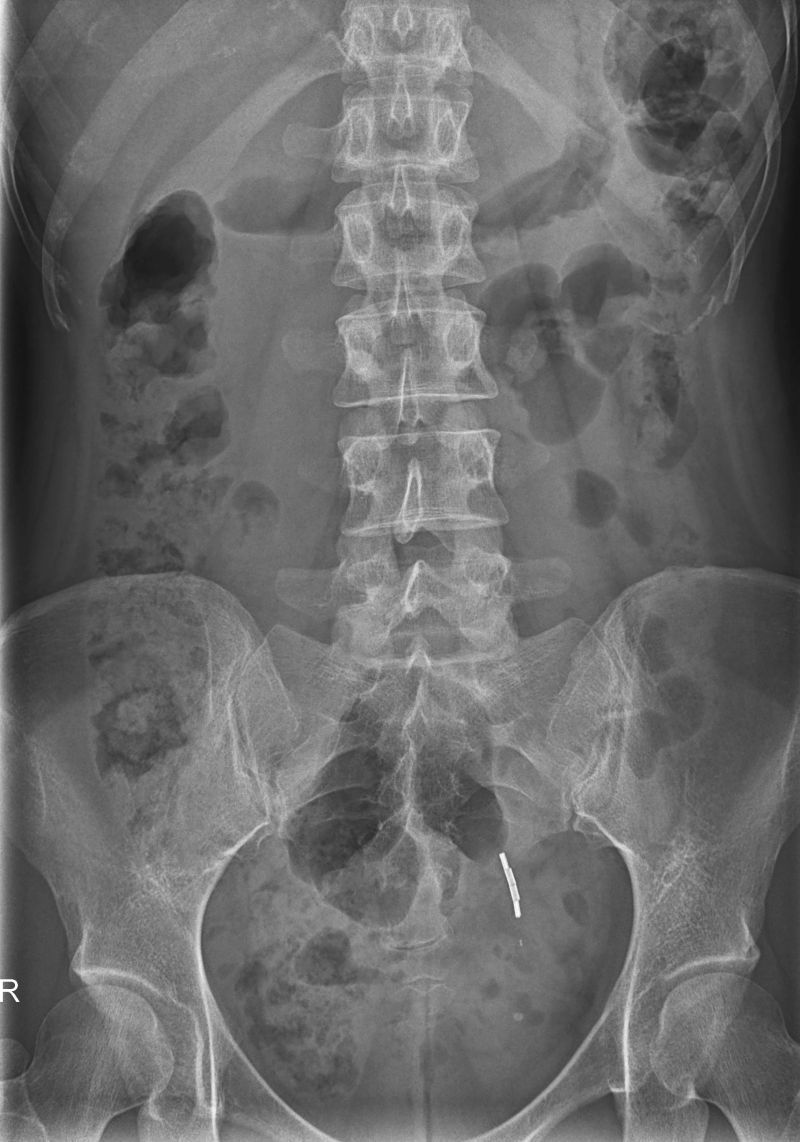

Die Röntgenstrahlung wird durch verschiedene Organe unterschiedlich stark geschwächt. Diesen Effekt macht man sich bei den verschiedenen Röntgenuntersuchungen zu nutze: Dichte Strukturen wie Knochen werden hell dargestellt, weil sie die Röntgenstrahlung stärker schwächen als weniger dichte Gewebe wie Muskel- oder Lungengewebe, die daher dunkler abgebildet werden.

Am häufigsten werden Röntgenaufnahmen von der Lunge, den Knochen und Gelenken sowie des Bauchraumes durchgeführt.

Röntgen des Bauchraumes

Beim Röntgen des Bauchraumes schaut man sich die Verteilung der Luft in den Darmschlingen an, die einen Hinweis auf z.B einen Darmverschluss geben kann. Findet man Luft im Bauchraum außerhalb des Darmes kann das ein Hinweis auf eine Perforation, ein Darmduchbruch sein.

Außerdem nutzt man das Bauchröntgen zur Suche von Fremdkörpern, wenn z.B. eine Spirale bei Frauen im Ultraschall nicht mehr gefunden werden kann oder zur Lagekontrolle von eingelegten Kathetern.